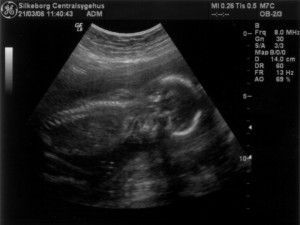

Ultralydsskanning den 21. marts 2006

Vi har i dag været på Silkeborg Centralsygehus, hvor Stine skal føde. Stine og baby blev skannet og alt var næsten som det skulle være. De var meget i tvivl om, hvorvidt der var en hjertefejl på barnet. Jordemoderen som foretig skanningen ville gerne have en overlæge til at vurdere billederne, men den eneste kvalificerede var i gang med en operation mens vi var der. Aftalen blev at de ville ringe til os, når overlægen havde set billederne. Da de ringede tilbage var deres svar at vi skal til Skejby for at få dem til at vurdere babys hjerte. Vi blev sat til at skulle skannes alleredde i morgen, da de mente at det ville være uansvarligt at lade os gå med den usikkerhed de havde skabt i flere dage. Tak! Det blev usikkerheden nu ikke mindre af... Ud over den mulige hjertefejl, kunne de også konstatere at baby er en pige. Du kan se de billeder vi fik fra skanningen herunder.